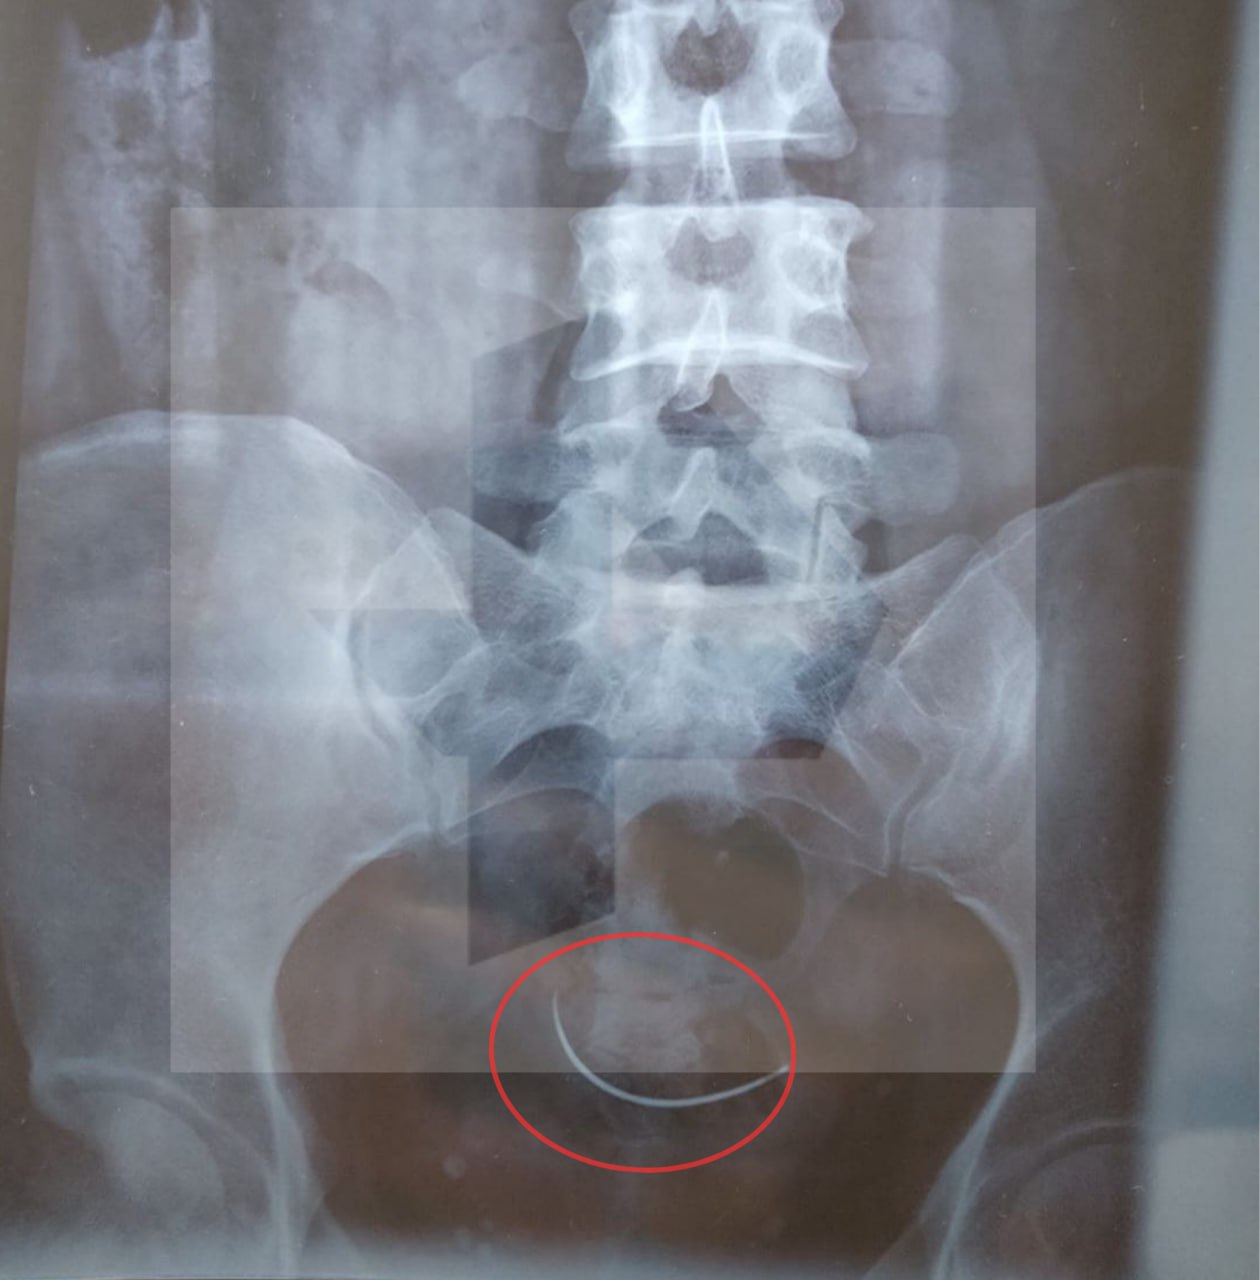

Пострадавшая даже не догадывалась, что в ее организме есть какой-то инородный предмет, пока три месяца назад не упала. На рентгене обнаружили, что в ее малом тазу находится медицинская игла.

У женщины было двое родов — в 2013 и 2018 годах, из которых вторые проходили путем кесарева сечения. Врачи центра, проводившие операцию 7 лет назад, уверяют, что игла осталась в теле именно после первых родов. Однако супруги не понимают, как женщина могла родить второго ребенка с таким предметом в организме и считают, что ошибка произошла в 2018 году.